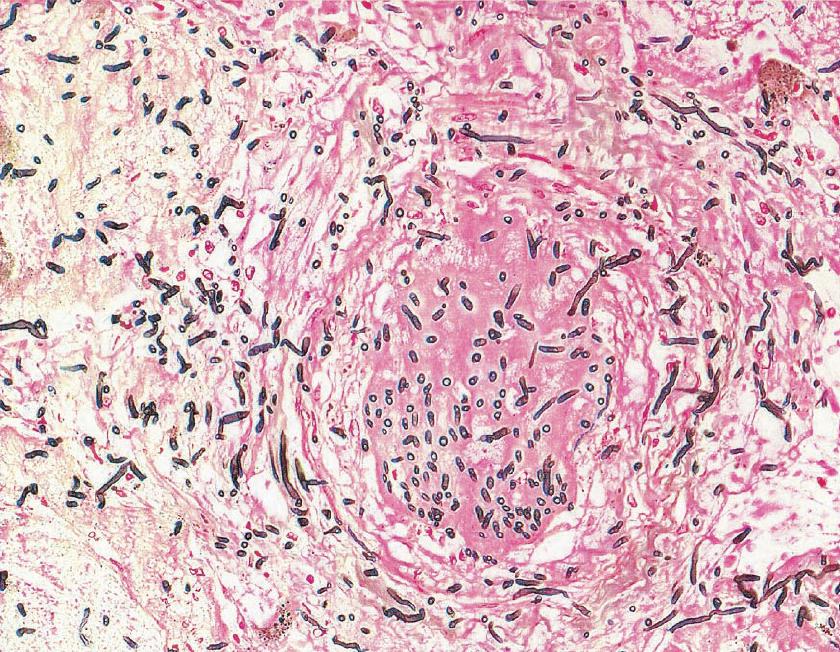

image

Действующее вещество препарата угнетает продукцию специального цитохрома, что в итоге приводит к нарушению биосинтеза эргостеролов и повышению внутриклеточной проницаемости. В результате воздействия Флуконазола большое количество электролитов и воды поступают в грибковую клетку, приводя к ее разрушению.